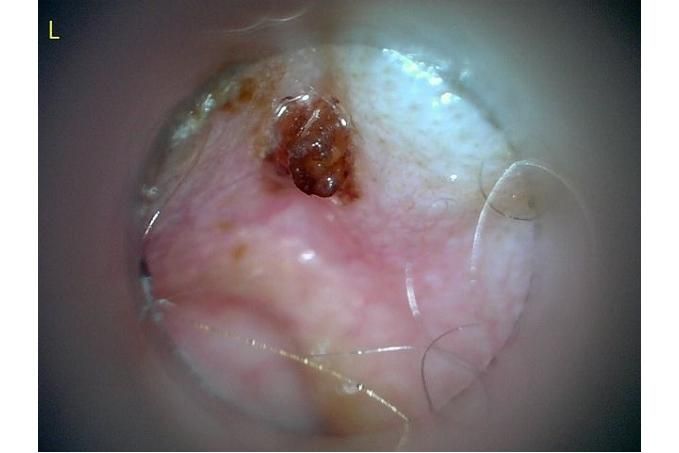

사진만 보고 확진할 수는 없지만 지금 올려주신 귀는 적어도 오른쪽은 정상으로 보이기 어렵습니다 왼쪽은 비교적 연분홍에 가까워 보이지만 오른쪽은 털과 분비물이 많이 차 있고 피부가 자극받은 듯한 모습이라 외이염 가능성을 먼저 생각하게 됩니다 그리고 질문자님이 적어주신 머리 털기 하루 여러 번 귀 만질 때 통증 솜만 닿아도 예민함 귀 긁기 같은 증상은 외이염에서 흔한 신호입니다

다만 이 사진만으로 중이염이나 내이염이라고 단정할 수는 없습니다 중이염이나 내이염은 귀 통증과 머리 털기만으로도 올 수 있지만 보통은 고개 기울어짐 비틀거림 안구가 흔들리는 증상 얼굴 한쪽 처짐 같은 더 깊은 신경 증상이 같이 보일 때 더 의심합니다 지금 적어주신 내용만 보면 제일 먼저는 오른쪽 외이도 염증과 통증 조절이 우선으로 보입니다